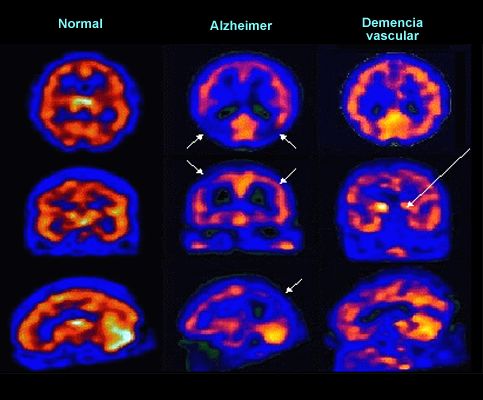

La gammagrafía de perfusión ayuda a distinguir la demencia vascular de la enfermedad de Alzheimer. En la demencia vascular, las áreas subcorticales suelen estar preservadas a diferencia de lo que ocurre en el Alzheimer.